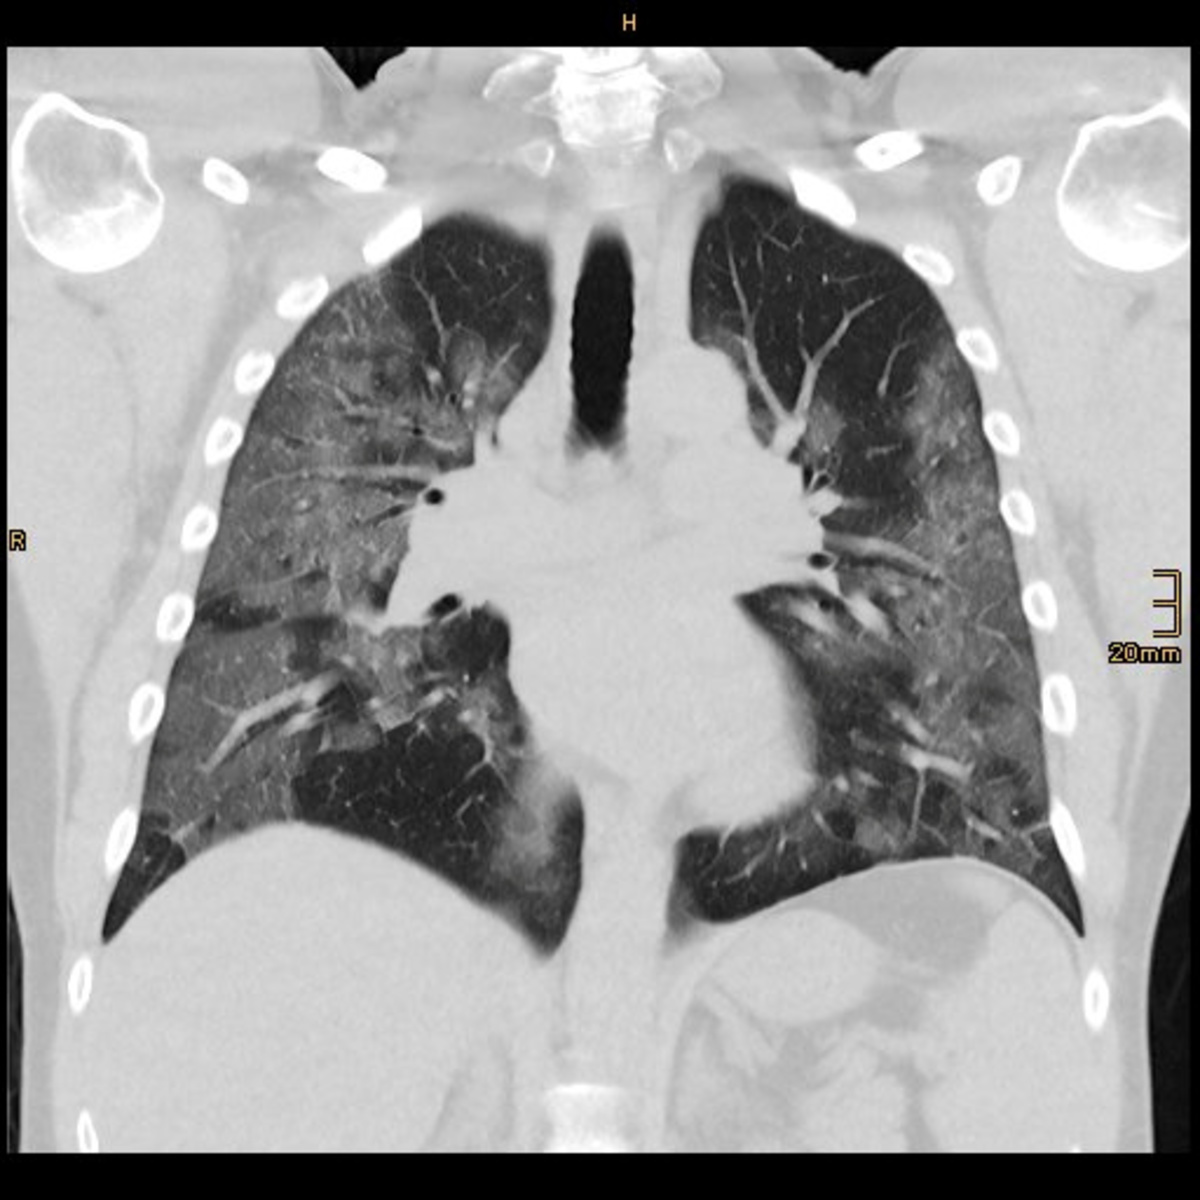

"I realised as soon as I saw the first CT scan ... that this had nothing to do with what we had seen and done for the past 40 years," he told Reuters.

In a paper published by the American Thoracic Society on March 30, Gattinoni and other Italian doctors wrote that COVID-19 does not lead to "typical" respiratory problems. Patients' lungs were working better than they would expect for ARDS, they wrote - they were more elastic. So, he said, mechanical ventilation should be given "with a lower pressure than the one we are used to."